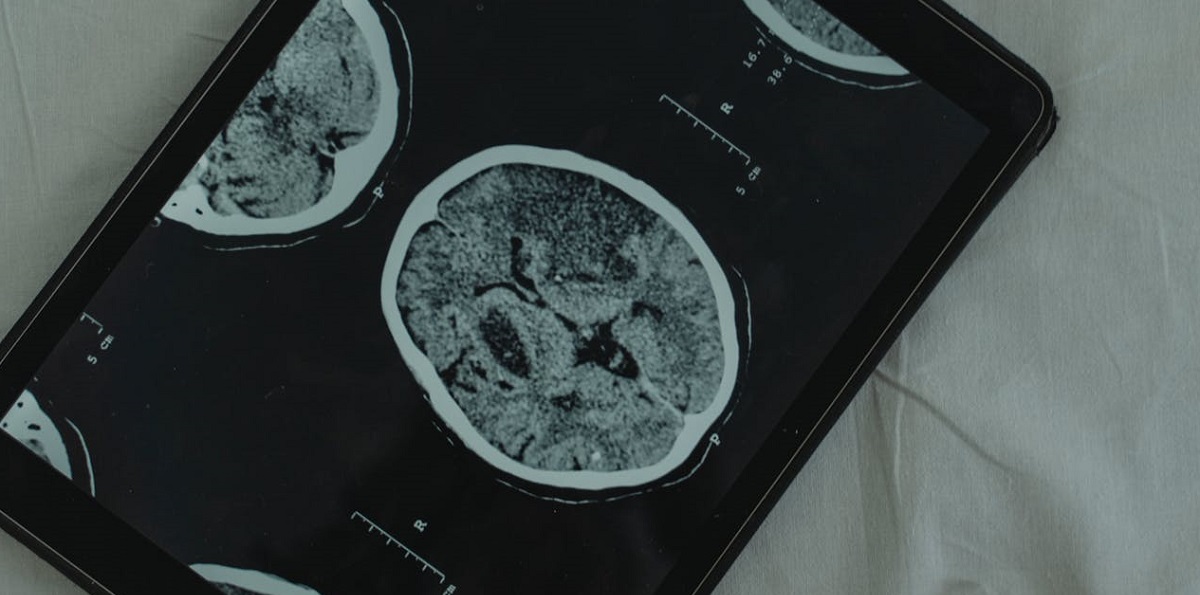

Il team di ricerca ha analizzato 1.111 scansioni di risonanza magnetica funzionale (fMRI) di persone con e senza demenza, utilizzando queste informazioni per creare un modello predittivo. Questo modello non solo identifica i segni rivelatori della demenza, ma lo fa con un’accuratezza dell’82%, offrendo una finestra temporale preziosa per potenziali interventi e trattamenti precoci.

Per sviluppare il modello, i ricercatori hanno raccolto scansioni fMRI dalla Biobanca britannica. Lo studio ha incluso 81 partecipanti a cui non era stata diagnosticata la demenza al momento delle scansioni, ma che hanno sviluppato la condizione fino a nove anni dopo. Questi partecipanti sono stati confrontati con 1.030 persone sane che hanno servito come gruppo di controllo. Analizzando le disconnessioni tra 10 regioni chiave all’interno del DMN, i ricercatori hanno utilizzato tecniche di apprendimento automatico per costruire il loro modello predittivo.